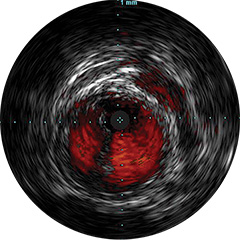

Figura 4